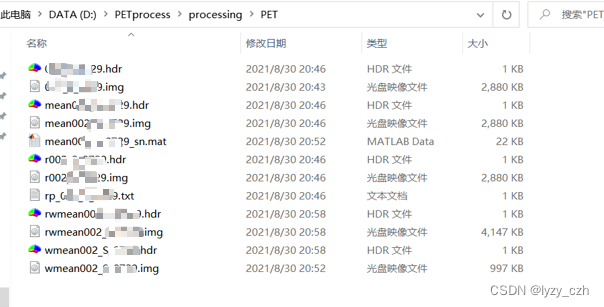

转换完成后输出如下:

这里生成了多个hdr/img的图像,只需要选择其中最好的一个即可(我看起来都是一样的)

此时在输出目录下生成如下文件:

生成如下文件:

生成如下文件: